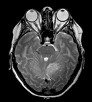

Figure 2.

T2WI at 3 months

T2WI at 6 months

T2WI at 12 months

SWIp at 12 months

Considering the pathognomonic aspects of LDD on both 3T MRI, spectroscopy and angiography, and since the patient was asymptomatic, we show that biopsy is not necessary to make the definite diagnosis. Follow-up at 12 months was negative and since no certain data regarding the doubling time of LDD are available we are considering that surgical treatment should be restricted both to patients with clinical deterioration due to the mass effect of the lesion and cases where the diagnosis based on clinical evolution and radiological findings is still uncertain.